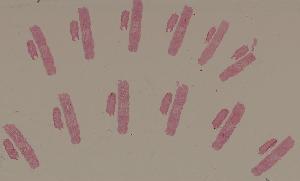

高倍视野

低倍视野